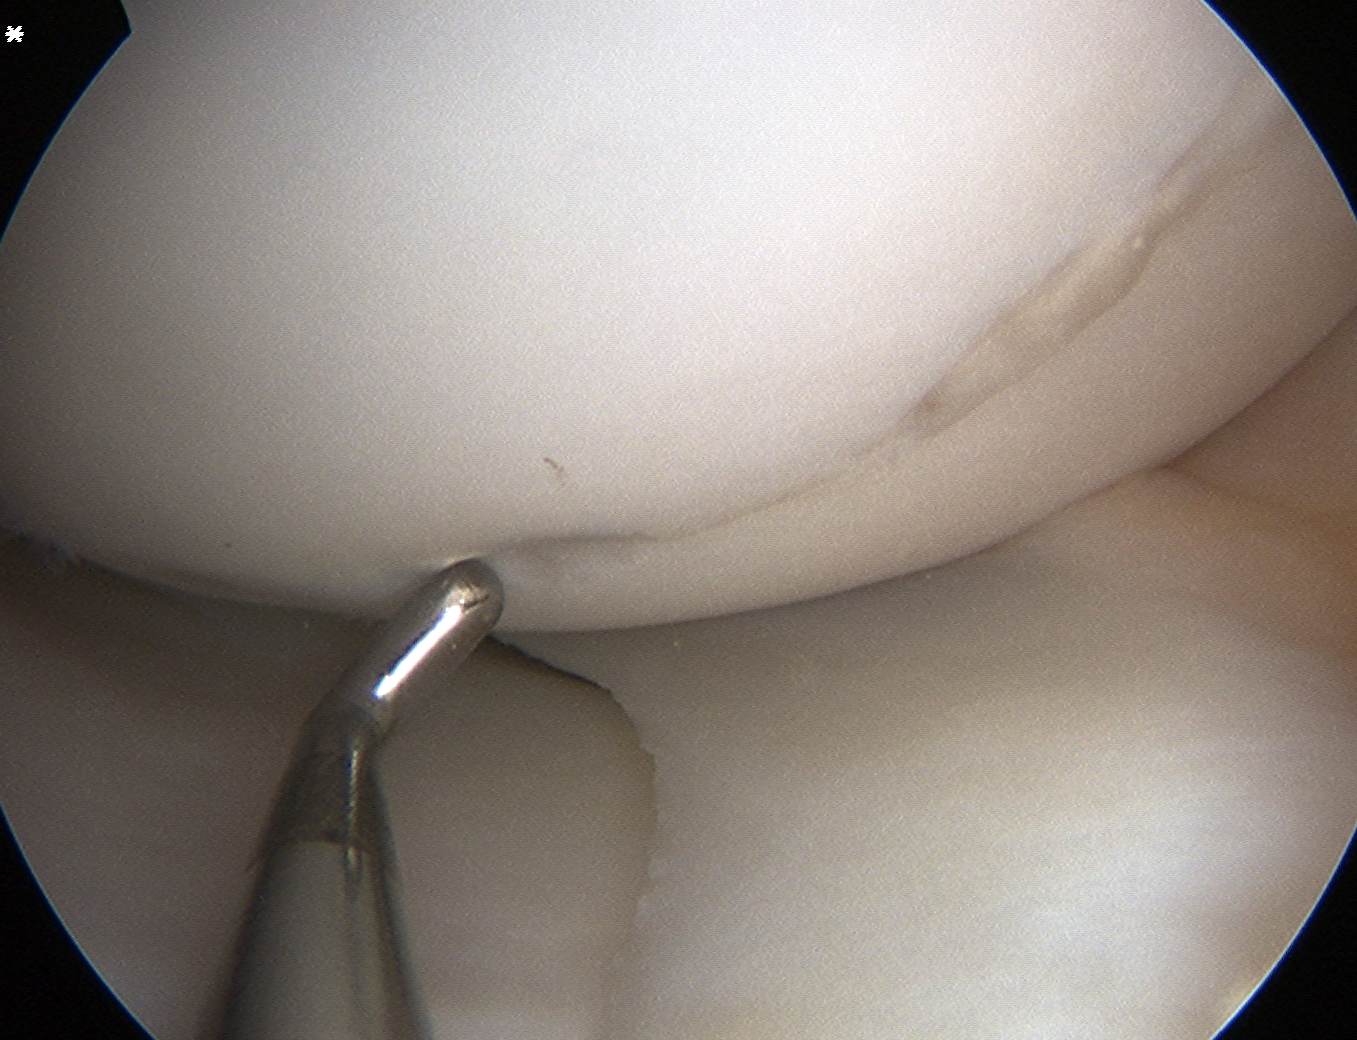

ICRS Arthroscopic Classification

1. Cartilage Intact

2. Partial discontinuity but stable on probing

3. Completely detached but insitu

4. Fully detached with crater & loose body